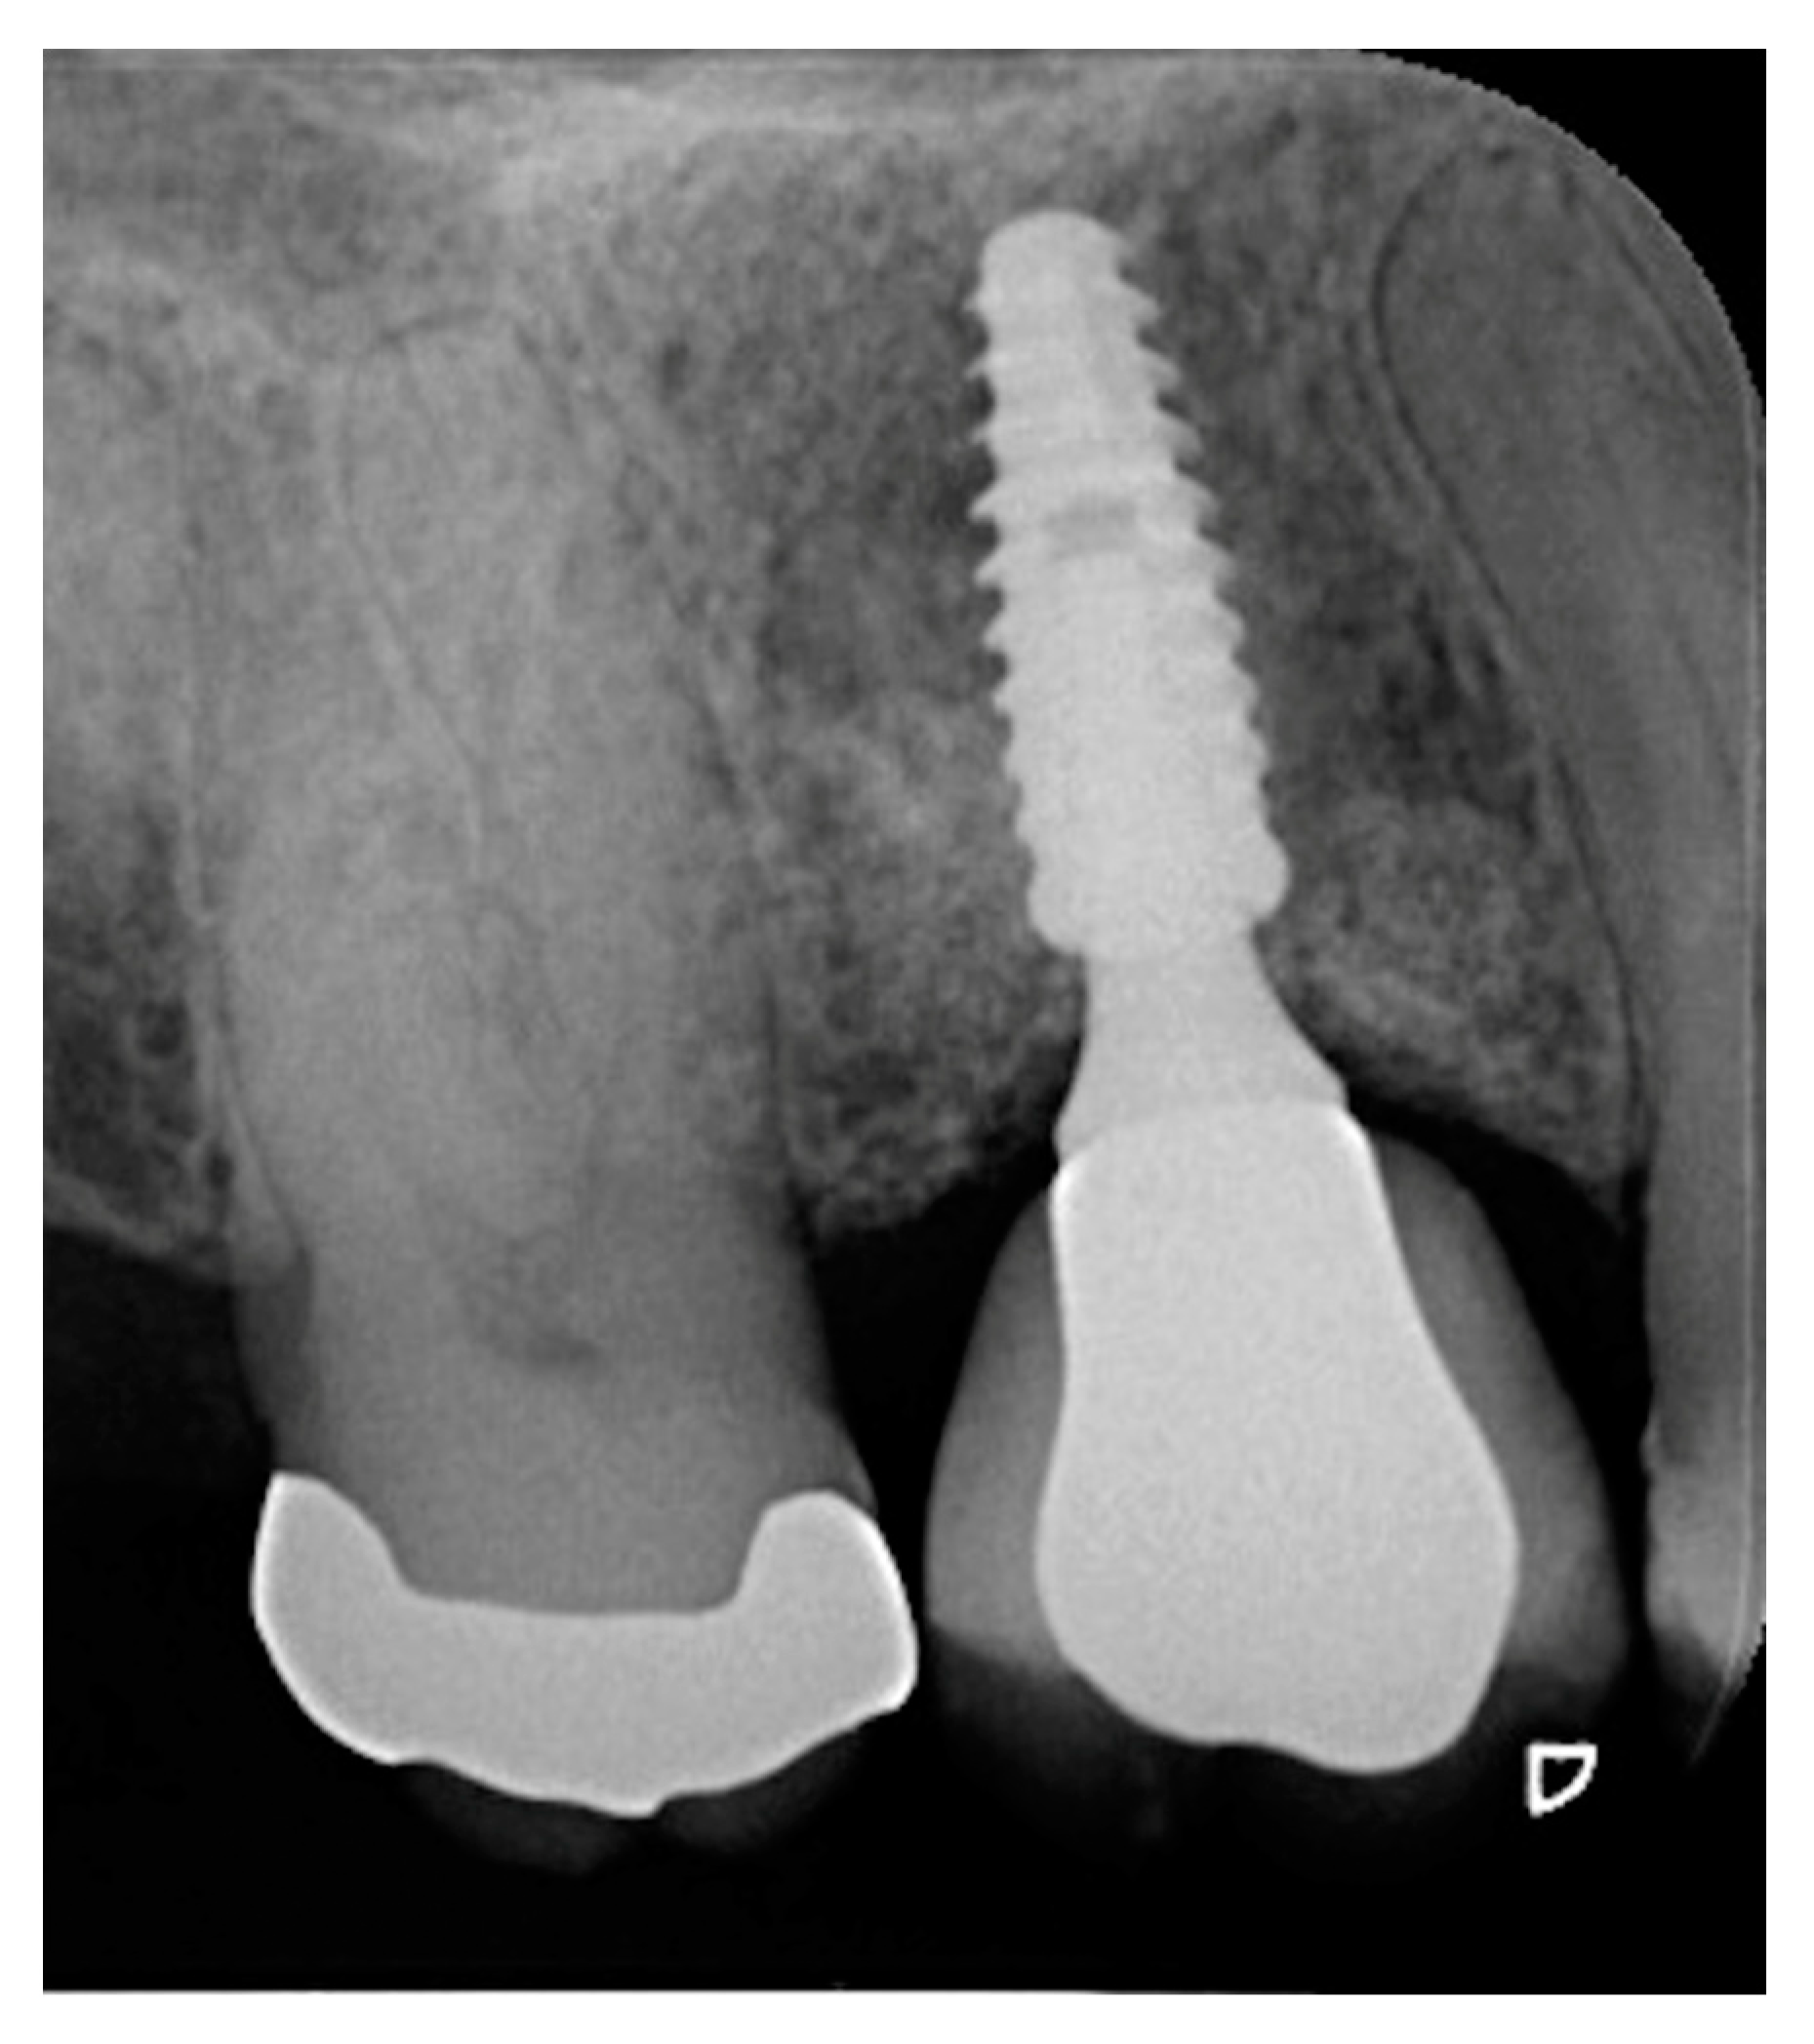

2. Materials and Methods

3. Results